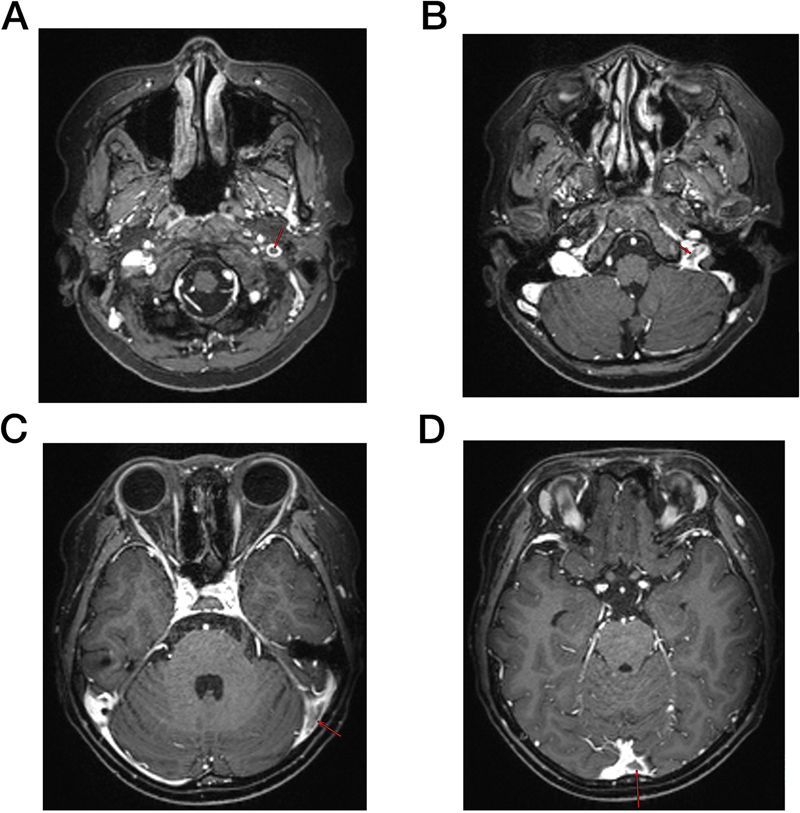

Cerebral venous sinus thrombosis (CVST) and hyperlipidemia are severe complications of L-Asparaginase (L-Asp) during the treatment of B-cell acute lymphoblastic leukemia (B-ALL). Herein, we reported a 9-year-old B-ALL boy who underwent abnormal hypertriglyceridemia and CVST presenting as seizures and disturbance of consciousness twice during the induction therapy. Fortunately, he survived treatment with anticoagulant and lipid-lowering therapy. No thrombophilia-related gene mutation was detected, but a heterozygous mutation in lipoprotein lipase (LPL) gene was identified. His neurological symptoms were managed with short-term anticoagulant therapy and long-term lipid-lowering therapy. This case illustrated the manifestation and potential pathogenesis of CVST and highlighted the essentiality of screening baseline lipid profile and dyslipidemia- and thrombophilia-related gene mutation.